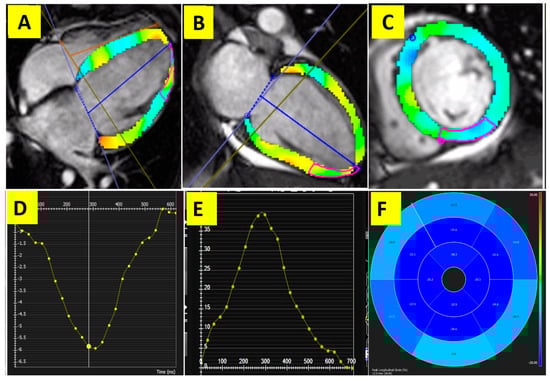

- Safaei, A.M.; Kamangar, T.M.; Asadian, S.; Rezaeian, N.; Esmati, E.; Kolahdouzan, K.; Hosseini, L.; Lashkari, M.; Jafari, F.; Hashemi, F.A. Detection of the Early Cardiotoxic Effects of Doxorubicin-Containing Chemotherapy Regimens in Patients with Breast Cancer through Novel Cardiac Magnetic Resonance Imaging: A Short-term Follow-up. J. Clin. Imaging Sci. 2021, 11, 33. [Google Scholar] [CrossRef]

- Asadian, S.; Rezaeian, N.; Hosseini, L.; Toloueitabar, Y.; Komasi, M.M.H.; Shayan, L. How does iron deposition modify the myocardium? A feature-tracking cardiac magnetic resonance study. Int. J. Cardiovasc. Imaging 2021, 37, 3269–3277. [Google Scholar] [CrossRef]

- Sharifian, M.; Rezaeian, N.; Asadian, S.; Mohammadzadeh, A.; Nahardani, A.; Kasani, K.; Toloueitabar, Y.; Farahmand, A.M.; Hosseini, L. Efficacy of Novel Noncontrast Cardiac Magnetic Resonance Methods in Indicating Fibrosis in Hypertrophic Cardiomyopathy. Cardiol. Res. Pract. 2021, 2021, 1–7. [Google Scholar] [CrossRef]

- Zhang, H.; Zhao, L.; Zhang, C.; Tian, J.; Ding, Y.; Zhao, X.; Ma, X. Quantification of Myocardial Deformation in Patients with Takayasu Arteritis by Cardiovascular Magnetic Resonance Feature Tracking Imaging. J. Magn. Reson. Imaging 2022, 55, 1828–1840. [Google Scholar] [CrossRef] [PubMed]

- Guo, X.; Liu, M.; Gong, J.; Yang, Y.; Liu, M.; Li, W.; Yang, Q. Left ventricular strain in patients with Takayasu arteritis with preserved ejection fraction: An analysis using cardiac magnetic resonance imaging feature tracking. Quant. Imaging Med. Surg. 2023, 13, 171–184. [Google Scholar] [CrossRef] [PubMed]